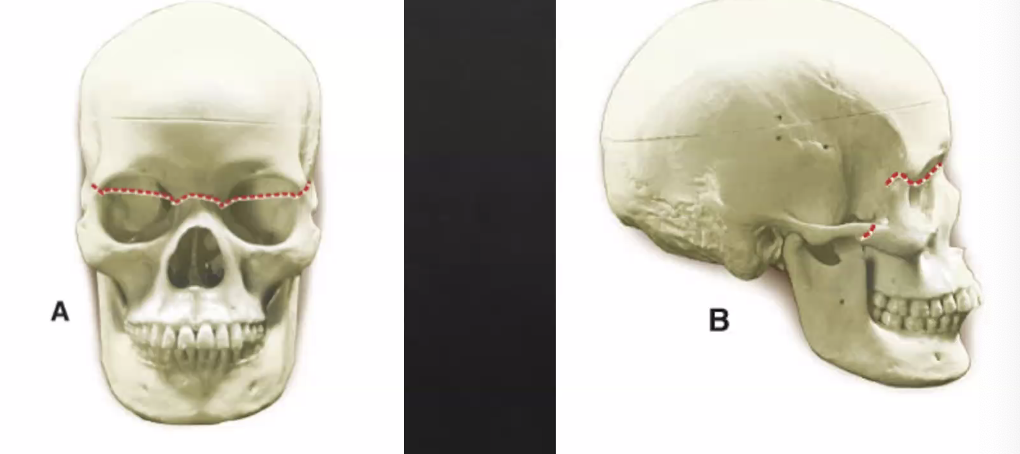

LeFort I

horizontal fracture of maxilla

least amount of force to cause fracture

LeFort II

pyramidal horizontal

fracture of maxilla and nose

LeFort III

craniofacial disjunction

bone is not stabilized and is mobile

face not attached to cranium

fracture near orbits

least common injury, with extreme force needed to occur